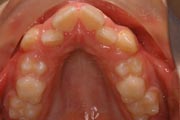

Crowding

Before